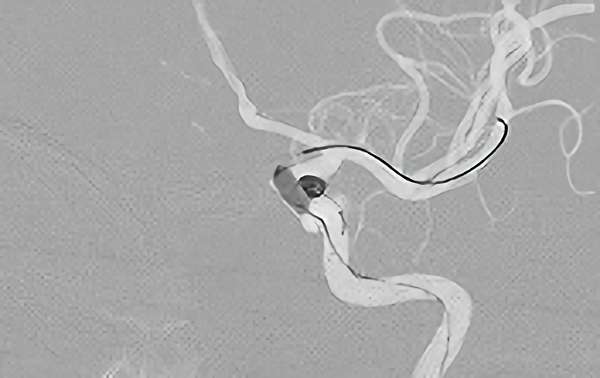

No.1618 手術中